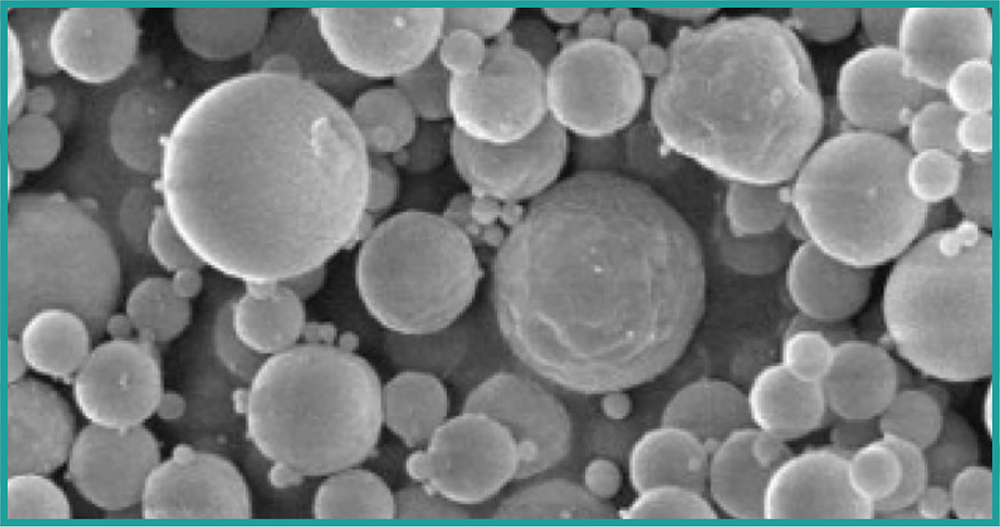

Figure 1: Direct manufacturing of particles suitable for inhalation.

Device and formulation interactions is another area of consideration for lung delivery. Any powder formulation will have to be of the relevant particle size for lung access, i.e. less than approximately 5 µm (Figure 2), which often makes powder “sticky” and prone to agglomerate and/or adhere to surfaces within the inhalation device. The patient’s inhalation force is used to disperse the powder during a short breath (1–3 seconds), which means that a certain minimum inhalation capacity is required to achieve efficient powder delivery. This is a concern for patients with severely diseased lungs, and sometimes liquid formulations delivered via nebulisers must be used instead.

Nanoform’s proprietary Nanoforming technology enables the production of small-molecule API nanoparticles without excipients and solvents. The manufacturing process is based on the precipitation of the API from a supercritical carbon dioxide (scCO2) solution, where precise process parameter control can lead to tight particle-size distribution and the desired crystalline or amorphous form. It is the only technology capable of manufacturing nanoparticles at the lower end of the nano range without solvents, excipients and complex production processes. Nanoparticles may be used in liquid suspensions or encapsulated into a spray-dried matrix for inhalation, either as individual nanoparticles or as submicron nanoclusters, e.g. to facilitate blending of different drugs in drug combinations or to tune drug dissolution rate.21

The platform process used for inhaled particles of standard excipients (including peptides and proteins) delivers material with similar characteristics as spray-dried material. These include a tight particle size distribution around a target of 2–3 µm, high dispersibility with fine particle fractions of up to 80% of the delivered dose and high drug loads in the range of 50–80% of the protein with a particle density suitable for efficient filling of standard capsules or blisters. Formation of protein aggregates was confirmed to be low using size exclusion chromatography, both post-processing and during storage.